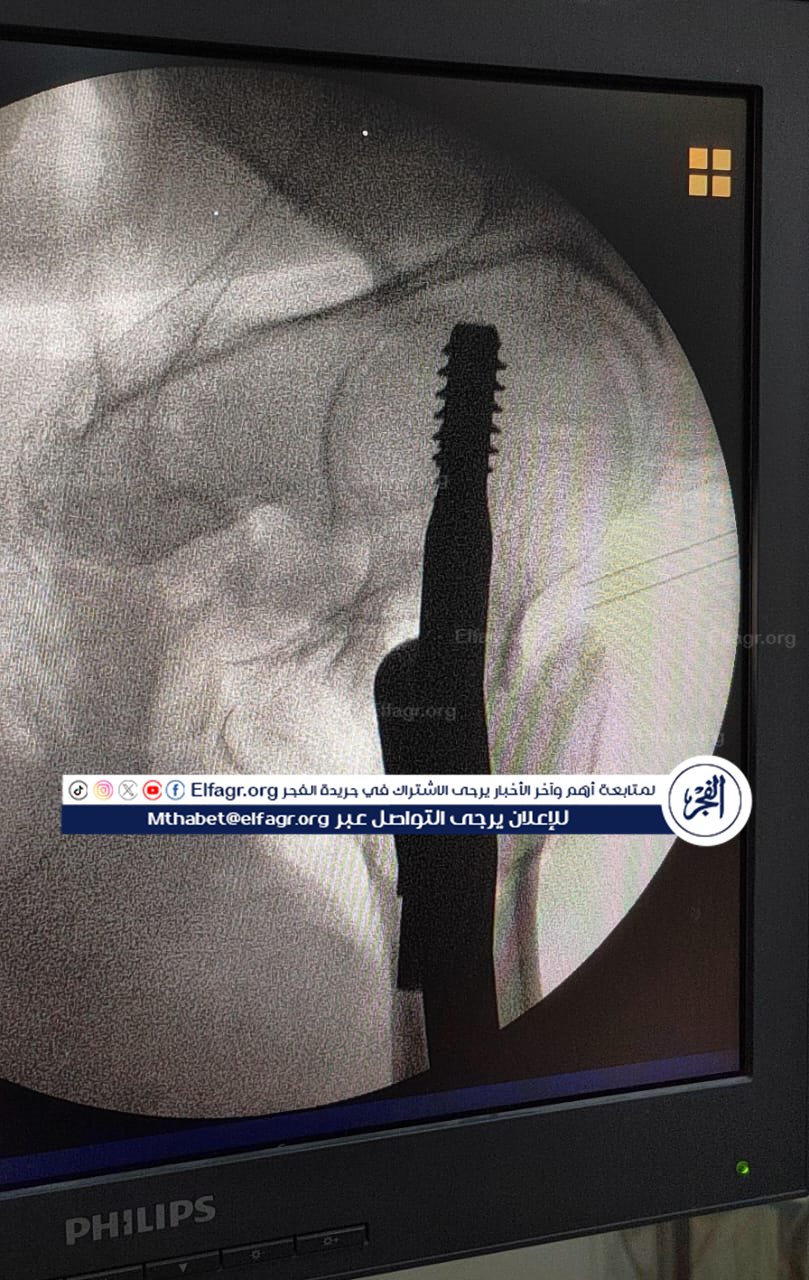

شملت العمليات تركيب كويرات بالرضفة اليسرى لمريض، وكذلك تركيب مسمار نخاعي بالفخذ الأيسر لمريض آخر، حيث تمت العمليتان بدقة عالية وباستخدام تقنيات حديثة ساهمت في تحقيق النتائج المرجوة.

جانب من الجراحة